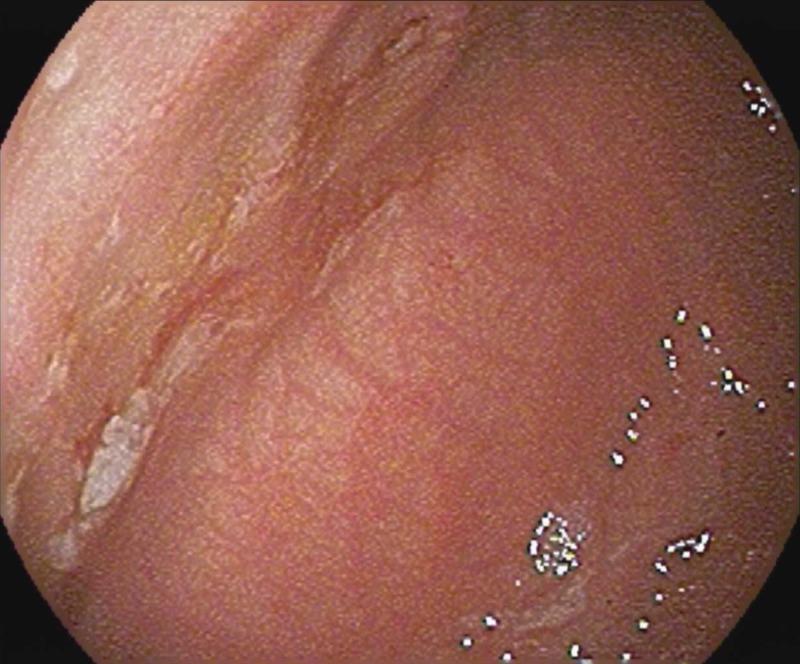

We present the case of a term-healthy neonate who developed hematemesis while being admitted at the newborn nursery. The infant was found to have gastric ulcers with duodenal eosinophils. The condition was conservatively managed and the symptoms, including ulcers, resolved with time; however, the etiology of the ulcers is still unknown.

我们报告一例足月健康新生儿的病例,该患儿在新生儿病房住院期间出现呕血。经检查发现该婴儿患有胃溃疡并伴有十二指肠嗜酸性粒细胞浸润。病情采用保守治疗,包括溃疡在内的症状随时间推移逐渐缓解;然而,溃疡的病因仍不明。